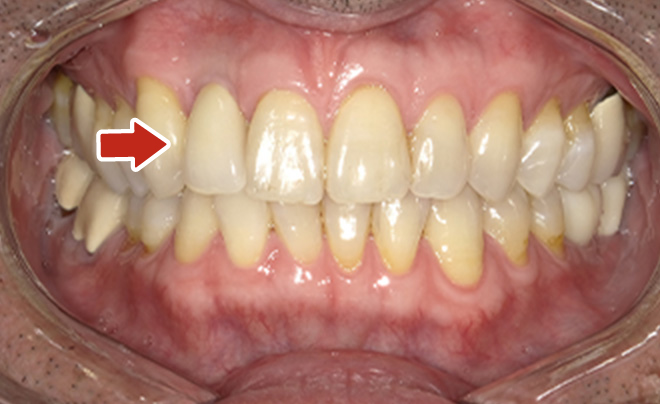

Before

After

| 68歳 男性 | 紹介 |

|---|---|

| 主訴 | れ歯が合わない 食べにくい 人生を豊かにしたい |

| 処置内容 |

上顎4本で12歯(オールオン4)、下顎4本5歯 上下抜歯即時埋入、即時荷重(手術当日にインプラントの上に仮歯装着) |

| 治療費用 | 上顎: 約220万(税込) 下顎: 約180万円(税込) |

| 治療期間 | 上顎: 9ヶ月 下顎: 6ヶ月 |

| リスク |

術後の腫れ、痛み(ピークは3日後、1週間で軽減) 上部構造物、仮歯の破折、人工歯根脱落リスクがあります |